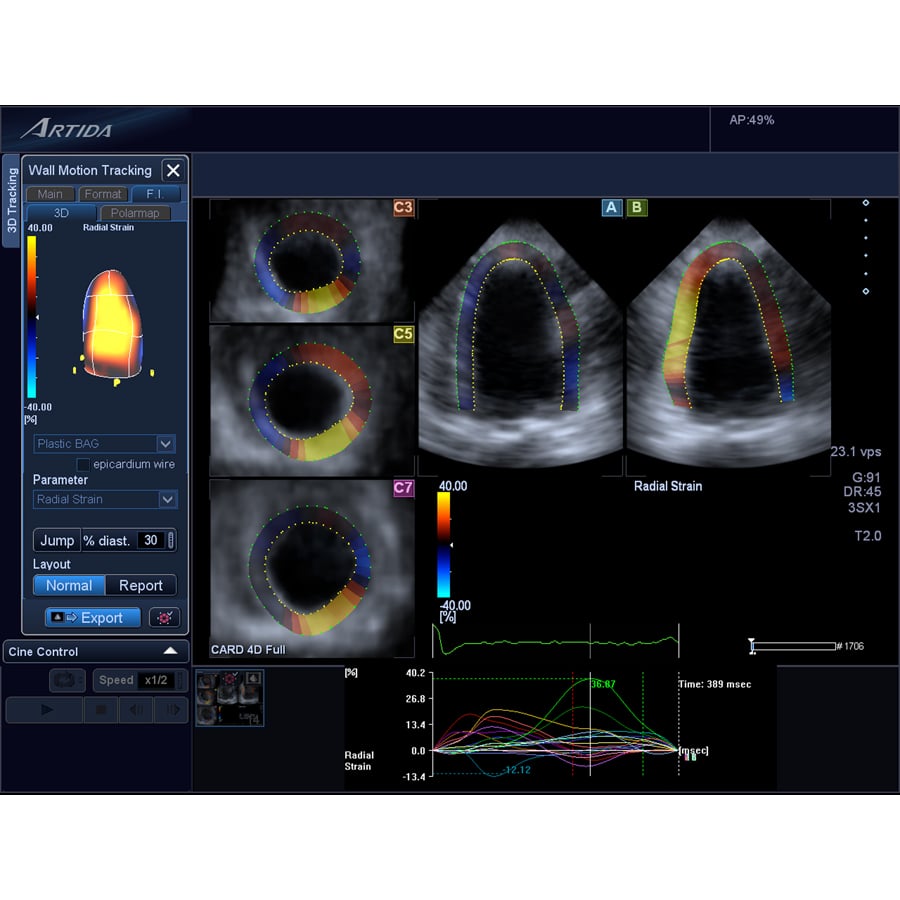

Cardiac imaging surveillance of cancer patients can be done using echocardiography, nuclear imaging or magnetic resonance imaging (MRI), said Storozynsky. However, echo is the easiest modality for most patients and centers to access, and is less expensive than nuclear or MRI. He said 3-D allows the calculation of very accurate ejection fractions. Live tissue Doppler allows imaging of cardiac function by allowing assessment of wall motion, and this can be enhanced using echo contrast.

One cardiac ultrasound innovation that is widely used to assess cancer patients’ hearts is echo strain imaging. This advanced visualization software allows simultaneous assessment of three different views of the myocardium. The software allows quantification of the amount of left ventricular (LV) systolic function muscle strain in each view. Storozynsky said strain imaging can show microscopic changes in movement of the myocardium prior to the presentation of symptoms.